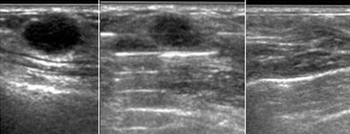

앞서 지난 2008년 여성외과를 운영하는 A원장은 유방 관련 질환을 검사하기 위해 맘모톰을 이용했으나, 종양이 발견돼 바로 절제한 후 '유방양성종양절제술'로 심평원에 청구했다.

B, C원장에게도 비슷한 사례로 과징금 부과처분이 내려졌다. 이들 원장은 답변서를 통해 "의료기기 허가사항을 관장하는 식약처에서도 양성 조직제거에 사용할 수 있도록 했다"며 "이러한 고시에 따라 맘모톰 기기를 이용해 검사목적의 침생검이 아닌, 치료목적의 양성종양 절제수술을 해왔다"고 주장했다.

또 "수술용 칼을 이용해 수술하는 것보다 맘모톰을 이용하면 시간적, 절차적으로 매우 단축되고, 환자 본인 만족도도 높다"며 "단순 검사가 아닌 수술, 즉 치료를 해서 해당 수가를 청구한 것이 왜 잘못인지 이해가 가지 않는다"고 지적했다.

그러면서 정부 관계자는 "최근 독일에서 나온 맘모톰은 날카로운 기구가 장착돼 충분히 수술이 가능하긴 하다"며 "그럼에도 과정과 절차상의 문제가 완전하게 잘못됐기 때문에 그 책임에서 자유롭지 못할 것"이라고 말했다.